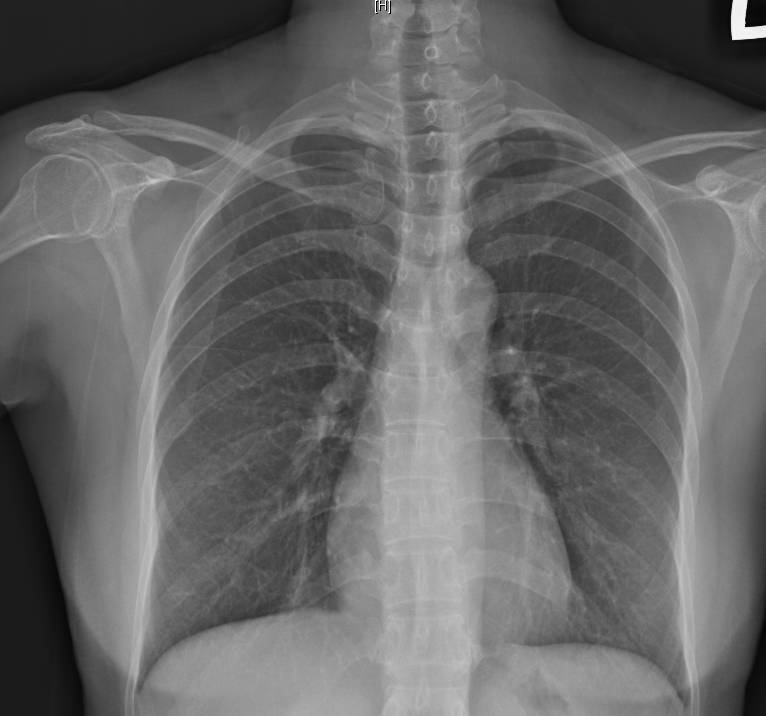

臨床案例顯示,一名33歲KTV領班在農曆年感冒康復後,仍持續乾咳近半個月,影響工作表現;另有61歲家庭主婦春節自日本返台後感冒,雖發燒與鼻塞等症狀改善,卻仍斷續乾咳將近一個月。經檢查胸部X光未見明顯浸潤或肺炎陰影,排除肺炎、肺癌與肺結核等重大疾病後,最終確診為感染後咳嗽。